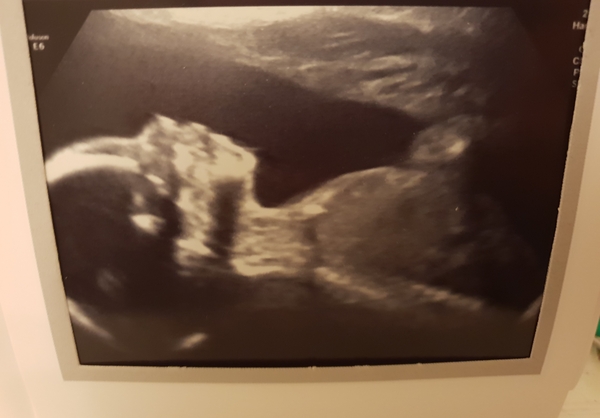

We had our scan yesterday and he's definitely a boy! He was so active, the sonographer joked that she was exhausted afterwards trying to get all the measurements and check everything πŸ˜‚ said I'll be bruised in a few weeks if he carries on the way he is. Little monkey. In the past week what I thought were movements have become more definite and she said he's still bouncing up and down on my cervix which he's done at all the scans! Kicks are now taking me by surprise they are so hard!

I've attached a pic but getting him to stay still long enough was a challenge!

Lovely scan @melissa112, he looks lovely and calm in the picture, like he was sleeping peacefully the whole time haha